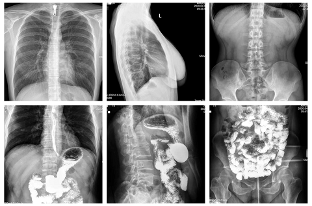

得益于安健科技多年来持续专注于数字化X线影像的技术突破与创新,安健科技目前已经掌握包括探测器、球管、高压发生器、精密机械制造与图像后处理技术在内的DR全部核心技术。腾灵在产品表现上得益于优质的影像链控制,搭载的高性能的非晶硅动态17*17英寸平板探测器,采集矩阵达3072*3072,高空间分辨率与高动态灰阶范围,为成像提供超大视野的同时保证优质成像质量。为了保证更好的图像处理效果,安健科技新一代IEAE高效率自动增强系统,包括智能感兴趣自动识别技术、金属识别技术、影像自动增强对比技术、影像伪影智能识别祛除技术以及动态滤波补偿技术等多项技术的加持,保证图像处理效果具备良好的一致性、对比度、层次感。

图3 腾灵临床图像采集